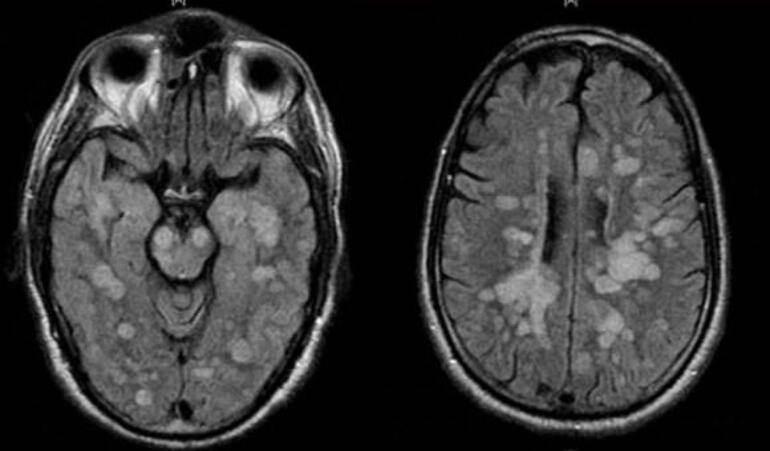

Talihsiz çocuğa vücudun bağışıklık sistemi kendisine saldırarak omurilik ve beynin şişmesine neden olan nadir bir akut yayılmış Ensefalit (ADEM) teşhisi koyuldu.

Tıp uzmanları, ilk olarak Haziran ayında koronavirüs ve ADEM arasındaki bağlantıyı kurmaya başladı.